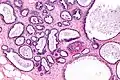

Фіброзно-кістозні зміни грудей, забарвлення H&E